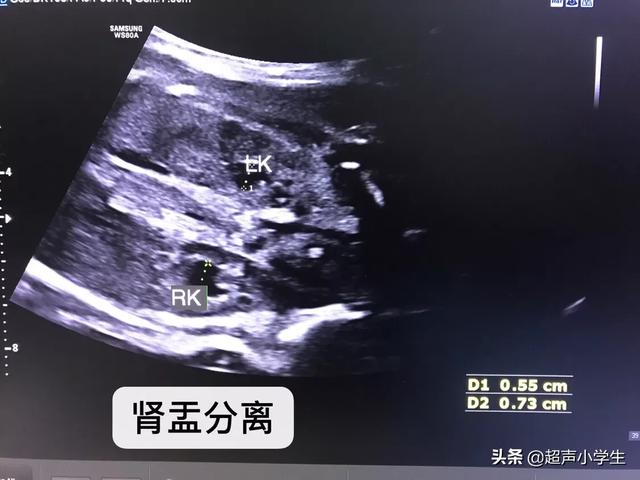

由于男女生殖系统的差异。发现肾盂分离的宝宝是男宝宝的可能性要大一些。特别强调只是可能性。也有女宝宝有肾盂分离的。只是说是男宝宝的概率大一点。